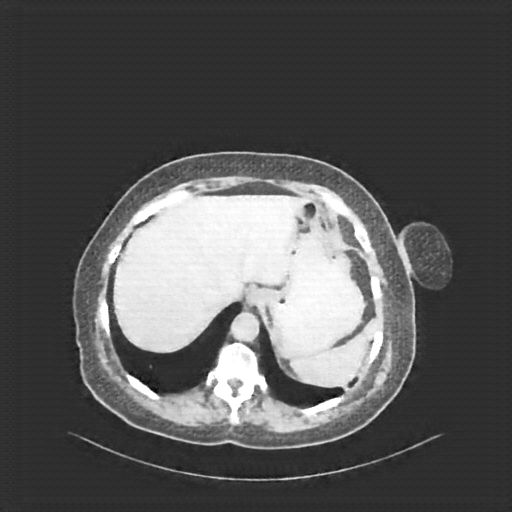

Original NATIVE CT scan (input)

Full window (WL 1023.5, WW 4095 β†’ Low βˆ’1024, High +3071)

Lung window (WL -600, WW 1500 β†’ Low βˆ’1350, High +150)

Mediastinum window (WL 40, WW 400 β†’ Low βˆ’160, High +240)